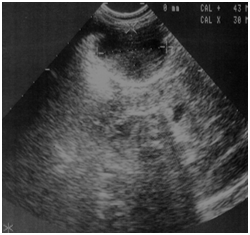

We report the case of a 28 days old girl with an antenatal diagnosis of abdominal mass. The physical examination was negative, blood sample results were within normal ranges (alpha-fetoprotein, bHCG and CA125). Urinalysis showed a small amounts of blood cells and leucocyturia, whereas the urine culture was positive for Escherichia coli (105). A micturitional cystourethrography and a complete abdominal ultrasound were performed. The micturitional cystourethrography showed a normal bladder for size and localization, with a lateral deflection of bladder imaging due to mass compression (Figure 1). The abdominal sonography showed a roundish mass with linear and exogenous margins, located in an anteromedian position compared to both the lower pole of the right kidney and the sub hepatic region. The mass was about 4x3x3 cm, and had a mixed solid -liquid echo structure (Figure 2) (Figure 3). A CT scan confirmed the presence of a 4cm cystic formation in the hepatic region but a subsequent MRI showed the mass in the right iliac fossa, and ruled out the involvement of other organs. In order to define a correct diagnosis and the subsequent surgical strategy we decided to perform a laparoscopic exploration. It was possible to identify a cystic mass in the sub-hepatic space with a diameter of 3-5cm. The mass was mobile, well delimited by the surrounding organs, with a thin long vascular pedicle (Figure 4). The exploration of the abdomen was normal and the left sided ovary and fallopian tube were normal. Although the diagnostic tests were negative, to completely rule out a neoplastic formation, the mass was totally removed through a minimal laparotomy to avoid dissemination of the fluid within the abdominal cavity in case of cyst rupture, according to the uncertain nature of che cyst. The histological diagnosis was “self amputated ovarian cyst” with necrosis and hemorrhagic fluid inside. The postoperative period was regular and the patient discharged on the second day after surgery.

Figure 4 Laparoscopic finding of the autoamputed ovarian cyst.